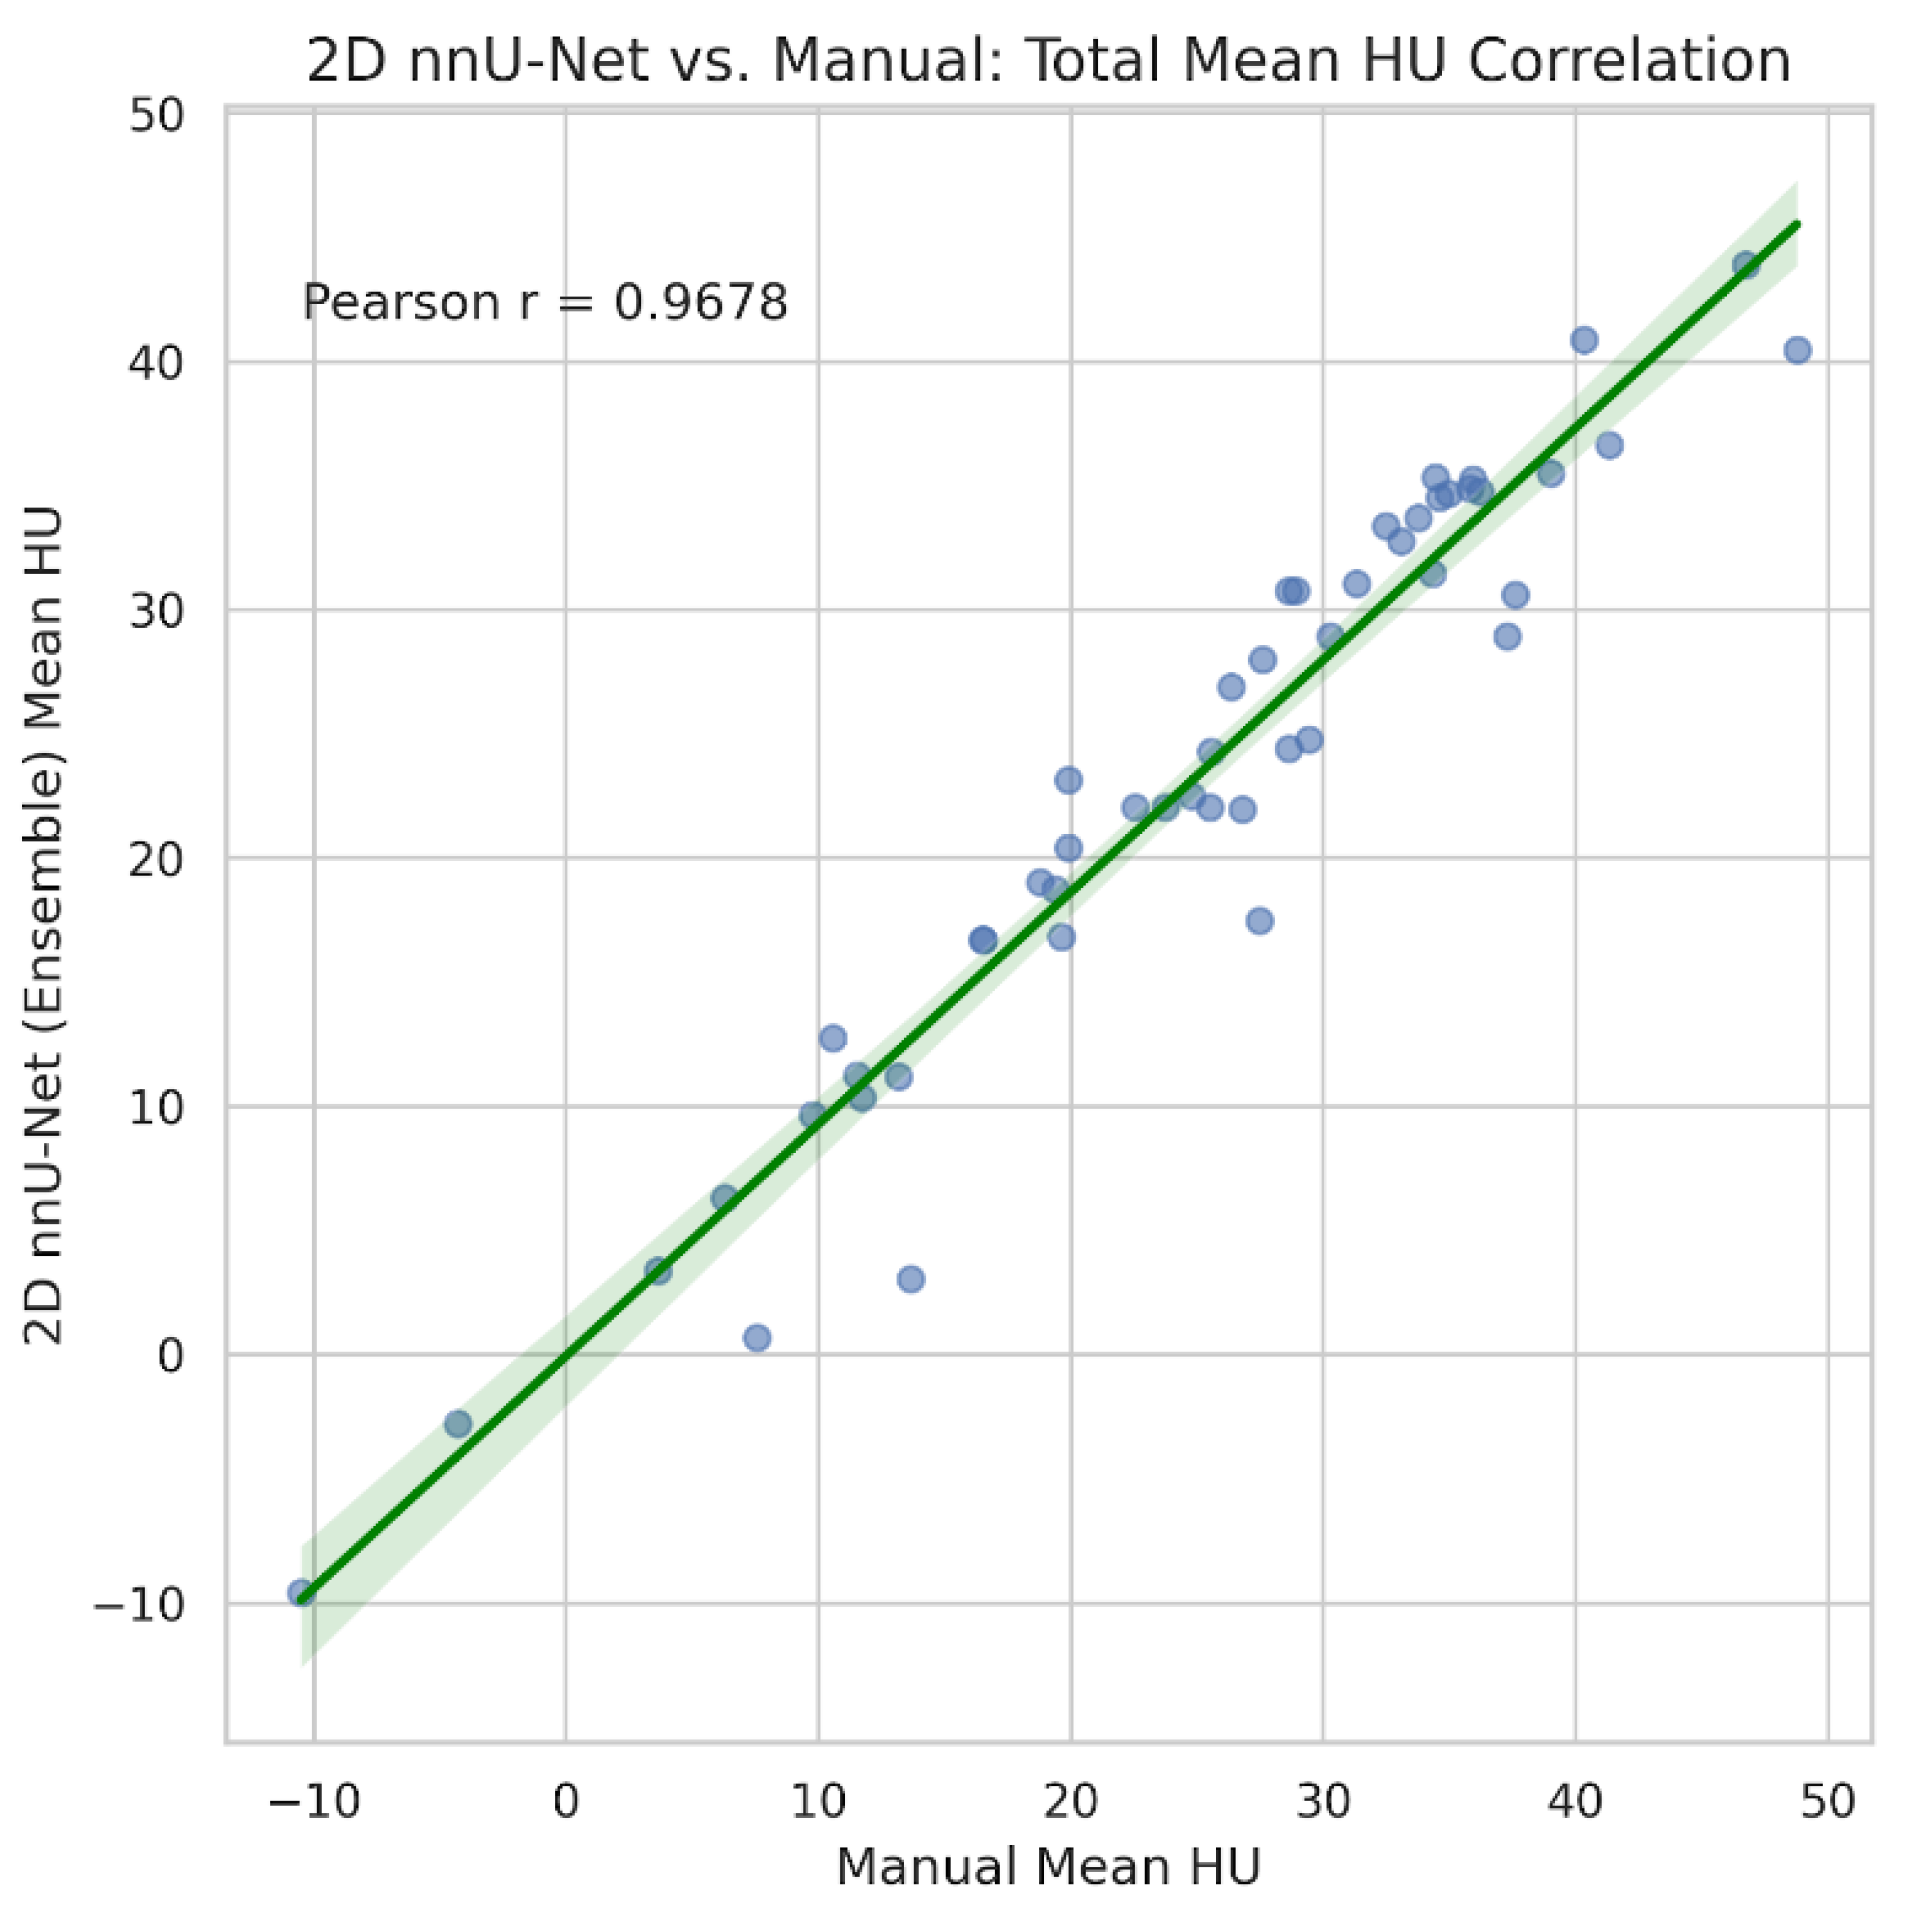

3.3. Clinical Agreement and Bias Analysis

| Metric | Pearson r | MAE | Mean bias (nnU-Net - manual) |

|---|---|---|---|

| Total muscle area (cm²) | 0.955 | 8.00 | +7.17 |

| Total mean attenuation (HU) | 0.968 | 2.33 | -1.67 |